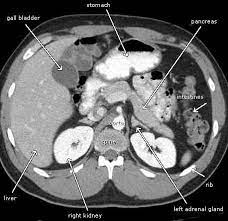

An abdominal CT scan is a powerful diagnostic tool that offers detailed images of the abdominal area. It helps in identifying the root cause of symptoms such as abdominal pain, swelling, or unexplained weight loss. For Priya, this was a practical solution to her emotional turmoil – the fear of not knowing what was happening inside her body.

For many like Priya, an abdominal CT scan is more than just a diagnostic test; it is a gateway to understanding one's health. It offers a practical solution to the emotional problem of uncertainty, allowing individuals to make informed decisions about their well-being. The peace of mind that comes from knowing what lies beneath the surface is invaluable.